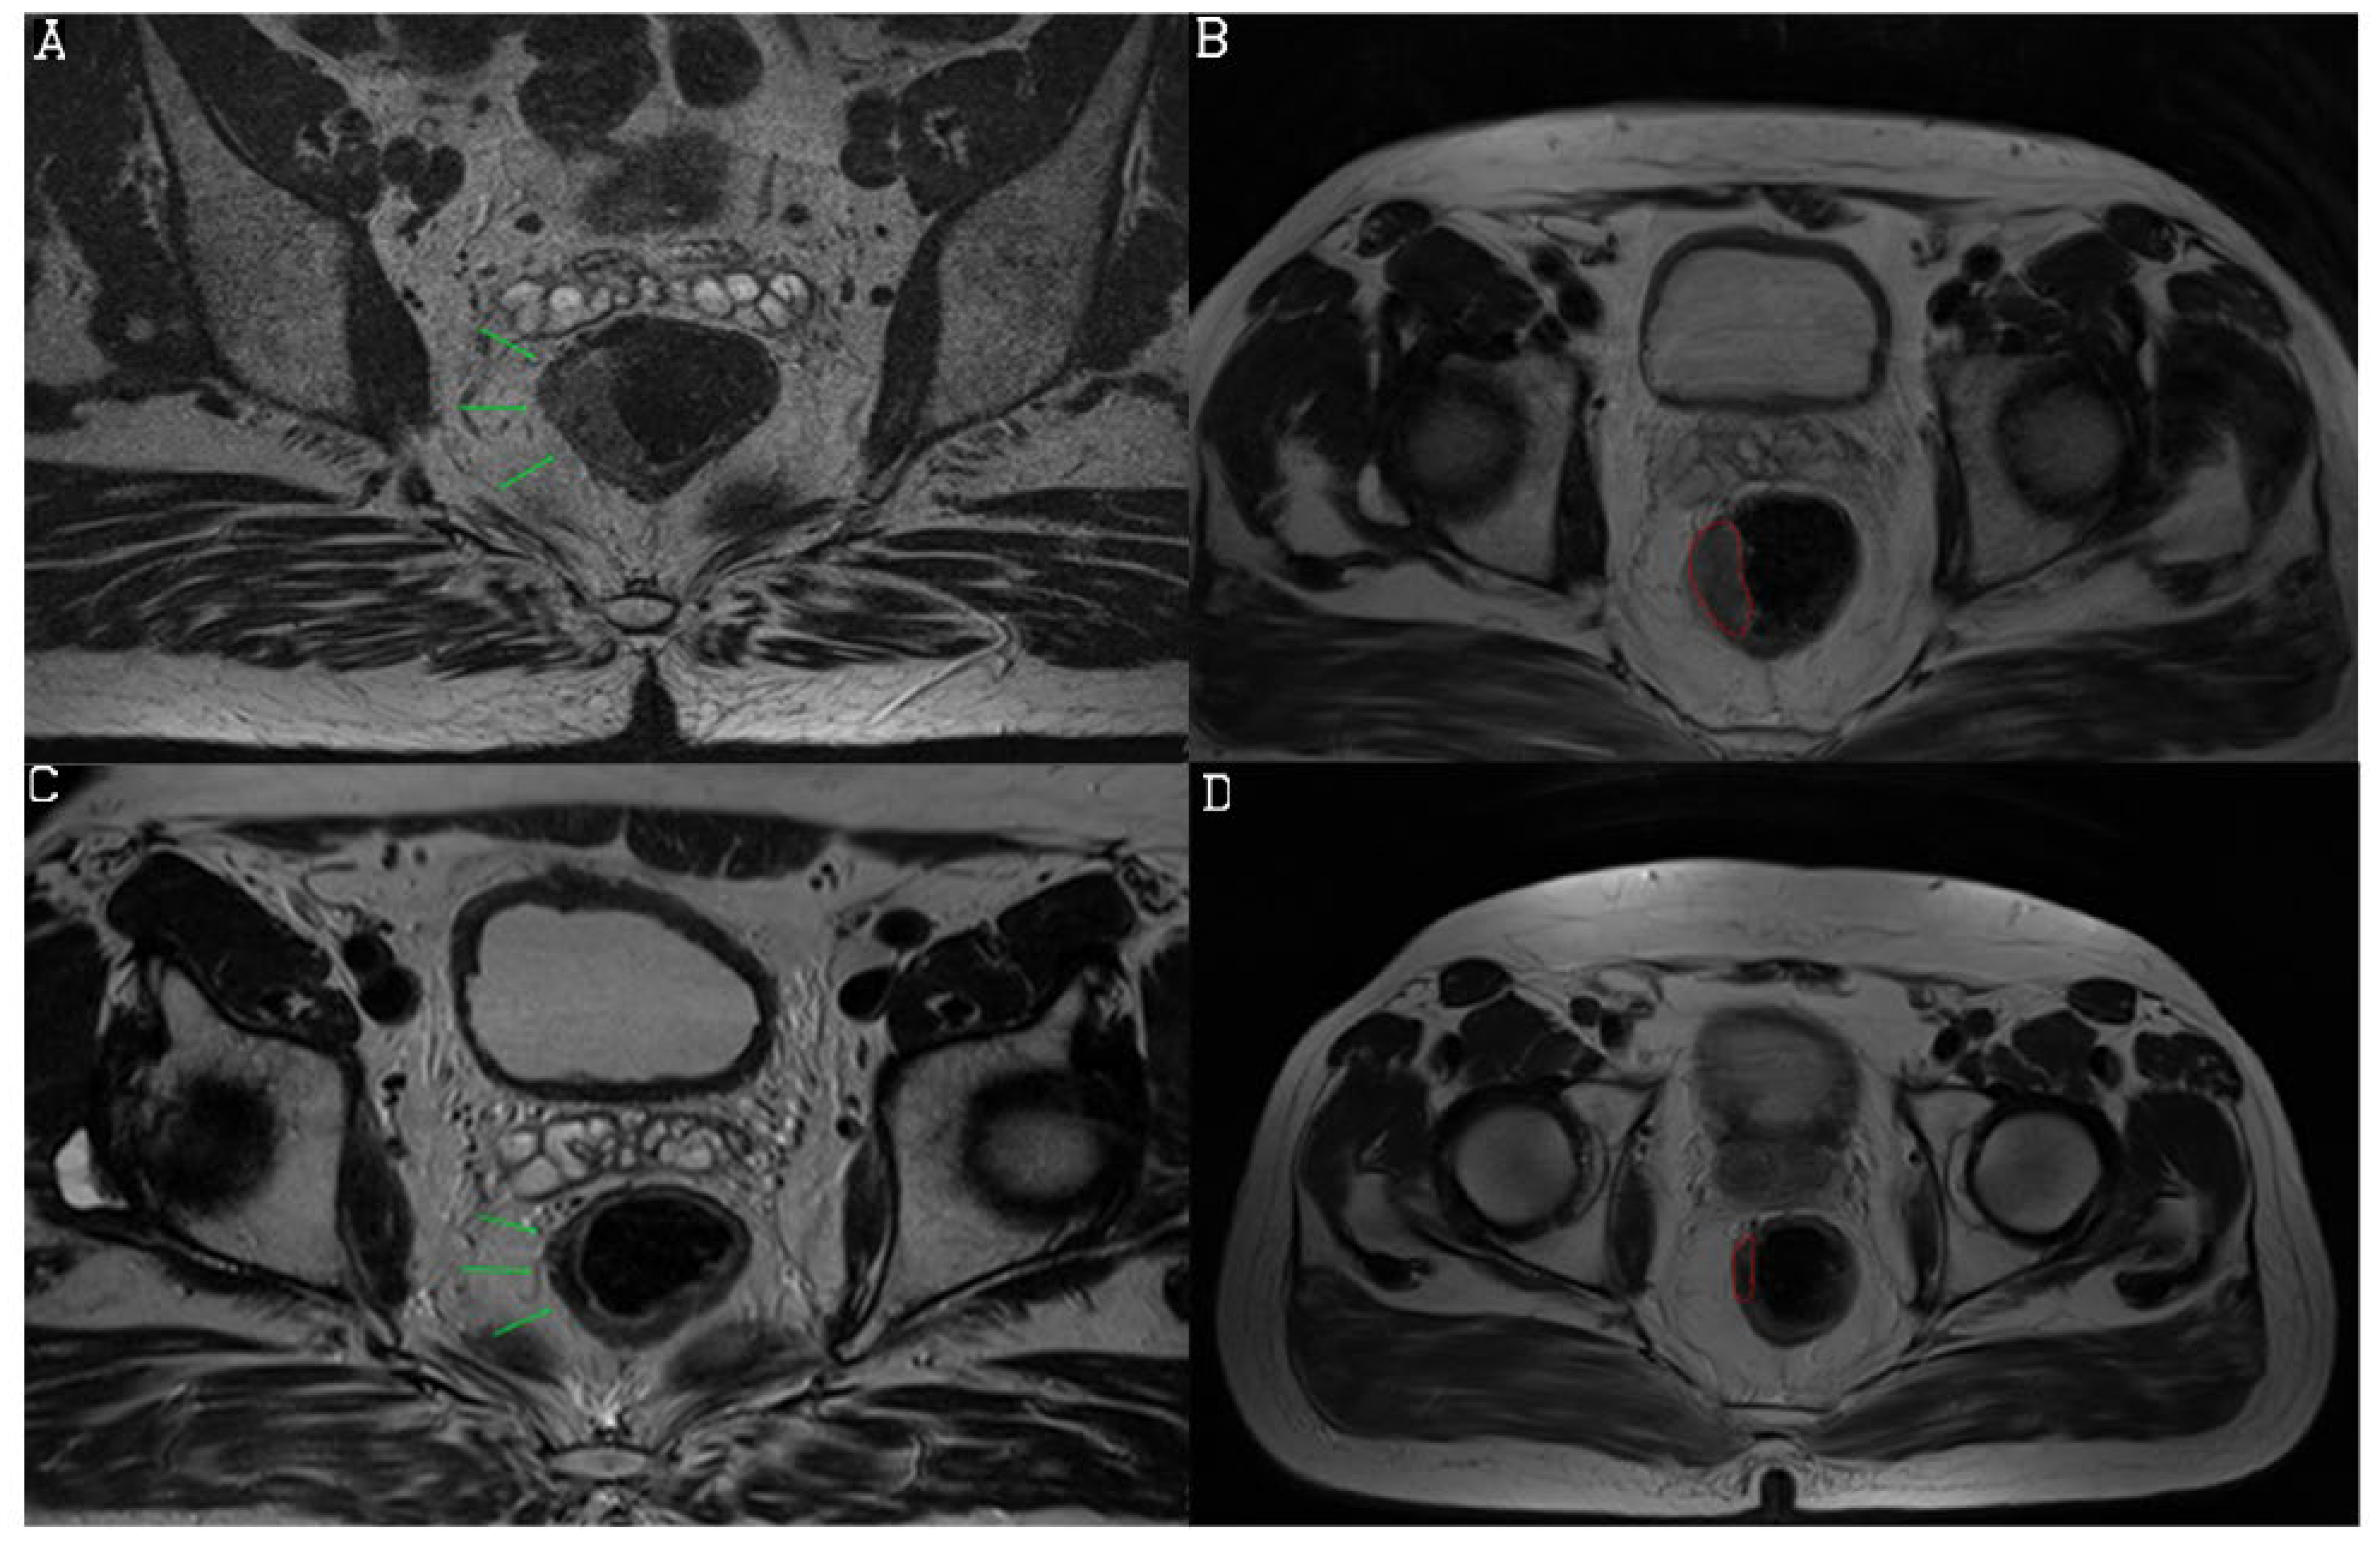

3.2. Diagnostic Performance of mrTRG